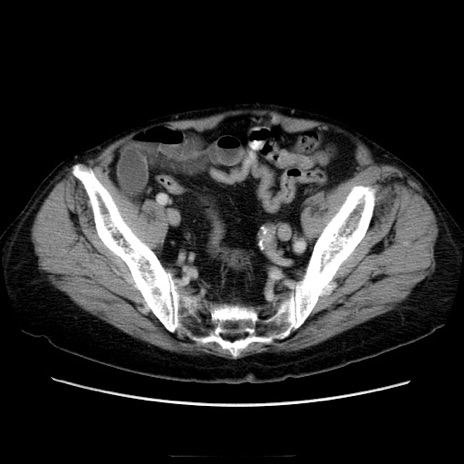

冠状断像